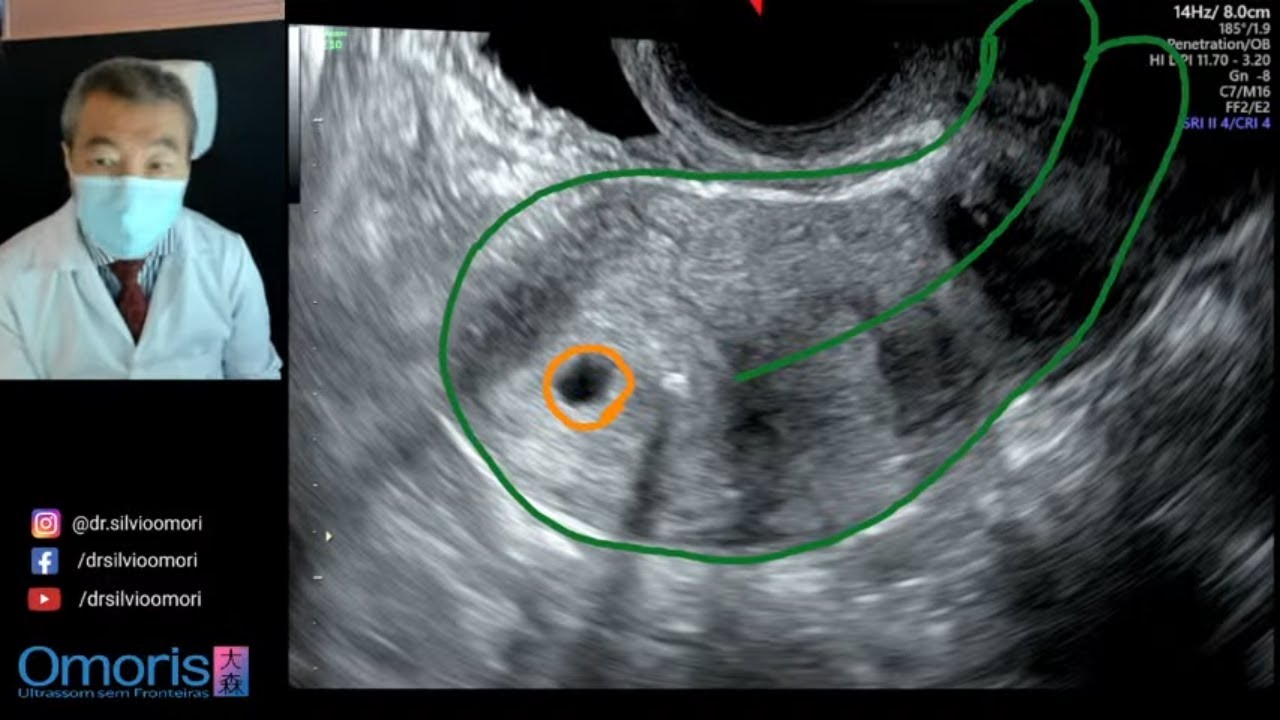

Ritardo Ciclo Con Spirale Rame. Web25.01.2021 07:55. [#1] entro 24 ore. Dr. Nicola Blasi Ginecologo 42.3k 1.3k 260. E’ importante valutare il posizionamento dello IUD ( spirale) con ecografia transvaginale per essere certi della ...

Ritardo Ciclo Con Spirale Rame. Ritardo Ciclo Con Spirale Rame, Anello anticoncezionale: NuvaRing, 1.08 MB, 00:47, 56,720, BIOFERTILITY ICSI-FIVET-Infertilità, 2018-02-06T15:40:31.000000Z, 3, Ejemplo De Reciclaje De Papel Del Ciclo Con Los árboles Ilustración del, es.dreamstime.com, 1300 x 1130, jpeg, Web25.01.2021 07:55. [#1] entro 24 ore. Dr. Nicola Blasi Ginecologo 42.3k 1.3k 260. E’ importante valutare il posizionamento dello IUD ( spirale) con ecografia transvaginale per essere certi della ... WebLa spirale in rame. Funziona per azione meccanica grazie a un sottile filo di rame che viene avvolto all´asta del dispositivo. ... Con la spirale può saltare il ciclo. Con., 20, ritardo-ciclo-con-spirale-rame, Informazioni sulle celebrità